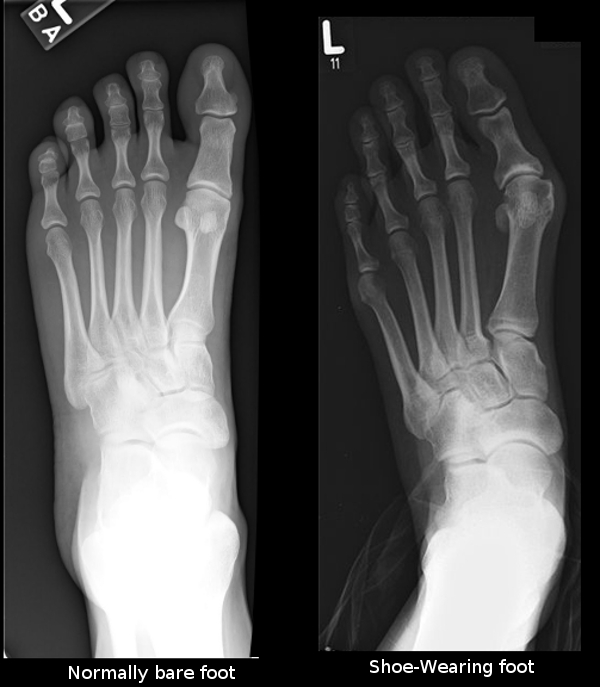

Unfortunately, as humans have started to wear shoes on a consistent basis it has taken a significant evolutionary toll on our physical bodies. Scientists have proven that non-shoe wearing people have significantly stronger immune systems, stronger bone structures, as well as better psychological dispositions than the chronically shod.

The evidence is clear and proven by the scientific community. Wearing shoes on a regular basis poses significant health risks to your body and immune system. Children who grow up barefoot generally have stronger feet, better flexibility and mobility. Barefoot children develop fewer deformities like flat feet or deformed toes. Studies have also shown that children that grow up barefoot have less health complications in later life stages.